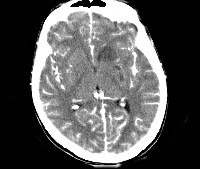

- Компьютерная и магнитно-резонансная томография. Позволяют оценить состояние головного мозга, выявить утолщение и уплотнение церебральных оболочек, изменения мозговых тканей. При наличии паразитов, на снимках будут визуализироваться гетерогенные круглые очаги с кольцевидным усилением по периферии;

• КТ, МРТ головного мозга. Определяется утолщение, уплотнение оболочек мозга, диффузные изменения церебральных тканей. Наличие воспалительных очагов визуализируется не всегда. При паразитарной этиологии характерны округлые очаги гетерогенной структуры с кольцевидным усилением по периферии.